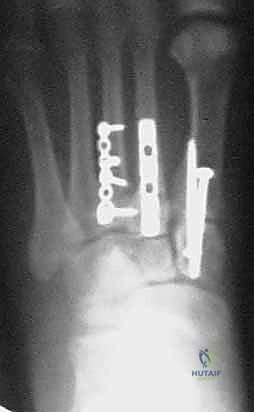

1. الرد المفتوح والتثبيت الداخلي (ORIF - Open Reduction and Internal Fixation)

هذا هو الإجراء الكلاسيكي والأكثر شيوعاً. يهدف إلى إعادة العظام إلى مكانها الطبيعي (الرد) وتثبيتها باستخدام معدات طبية (مسامير، شرائح، أو أسلاك) حتى تلتئم الأربطة والعظام.

خطوات العملية:

1. التخدير: يتم إجراء الجراحة تحت التخدير الموضعي (النصفي) أو العام.

2. الشق الجراحي: يقوم الدكتور هطيف بعمل شق جراحي دقيق (أو شقين) على ظهر القدم للوصول إلى المفاصل المصابة، مع الحرص الشديد على حماية الأعصاب والأوعية الدموية الدقيقة في تلك المنطقة باستخدام مبادئ الجراحة المجهرية.

3. التنظيف والرد: يتم تنظيف المفاصل من أي شظايا عظمية أو أنسجة محشورة تمنع عودة العظام لمكانها. ثم يتم إعادة العظام بحذر شديد إلى محاذاتها التشريحية الدقيقة (القوس الروماني).

4. التثبيت (Fixation): يتم تثبيت العظام باستخدام مسامير معدنية خاصة (Solid or Cannulated Screws) تعبر المفاصل لتثبيتها بإحكام. في بعض الحالات، يتم استخدام شرائح معدنية صغيرة للحفاظ على الاستقرار.

5. مسمار ليزفرانك: الخطوة الأهم هي وضع "مسمار ليزفرانك" (Lisfranc Screw) الذي يمر من العظم المسماري الإنسي إلى قاعدة المشط الثاني، لتعويض وظيفة الرباط الممزق.

6. الإغلاق: يتم إغلاق الشقوق الجراحية بعناية تجميلية ووضع القدم في جبيرة لحمايتها.